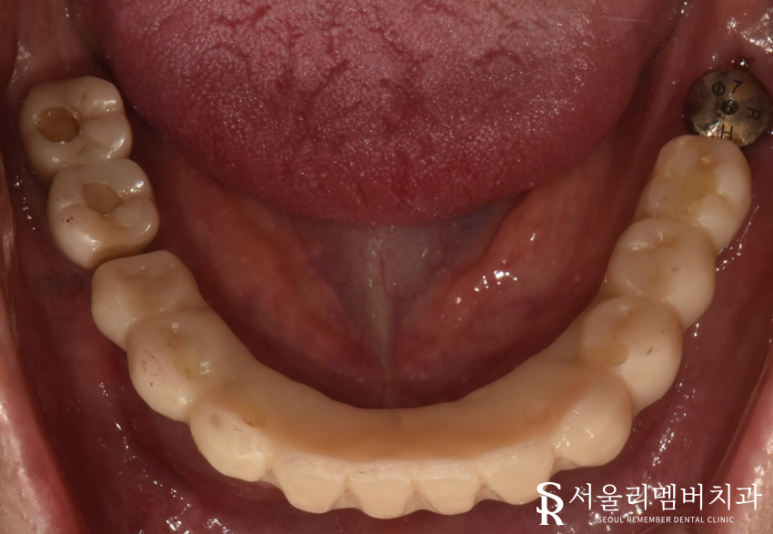

이후 생활하는 데에 불편함이 없도록 임시 보철을 올려드렸습니다.

몇 달 뒤, 최종 보철 세팅을 위해 다시 내원하셨는데요.

자 이제 결과가 어떻게 됐는지 확인을 해야겠죠?

이전에는 썩어있거나 이미 빠져버린 채 남아있던 치아들이

자연치와 유사한 외관을 자랑하는 지르코니아 크라운으로 꽉 채워져 있네요.